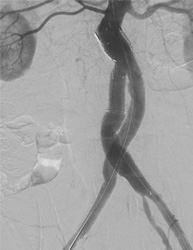

血管造影検査

従来、放射線診断に用いられていた血管造影はCTやMRIの発展にともない、現在では主として治療目的のために行われています。この手法はIVR(インターベンショナル・ラジオロジー)と呼ばれています。

当院の血管造影室には、全身用にAlluraXperFD20、心臓血管造影用にはAlluraXperFD10/10(いずれもフィリップス社製)が導入され、フルデジタル化により再現性の高いデータを迅速に参照できるようになり、より精度の高い検査と治療を行っています。

大動脈ステントグラフト

治療前   治療後

下肢動脈血管形成術